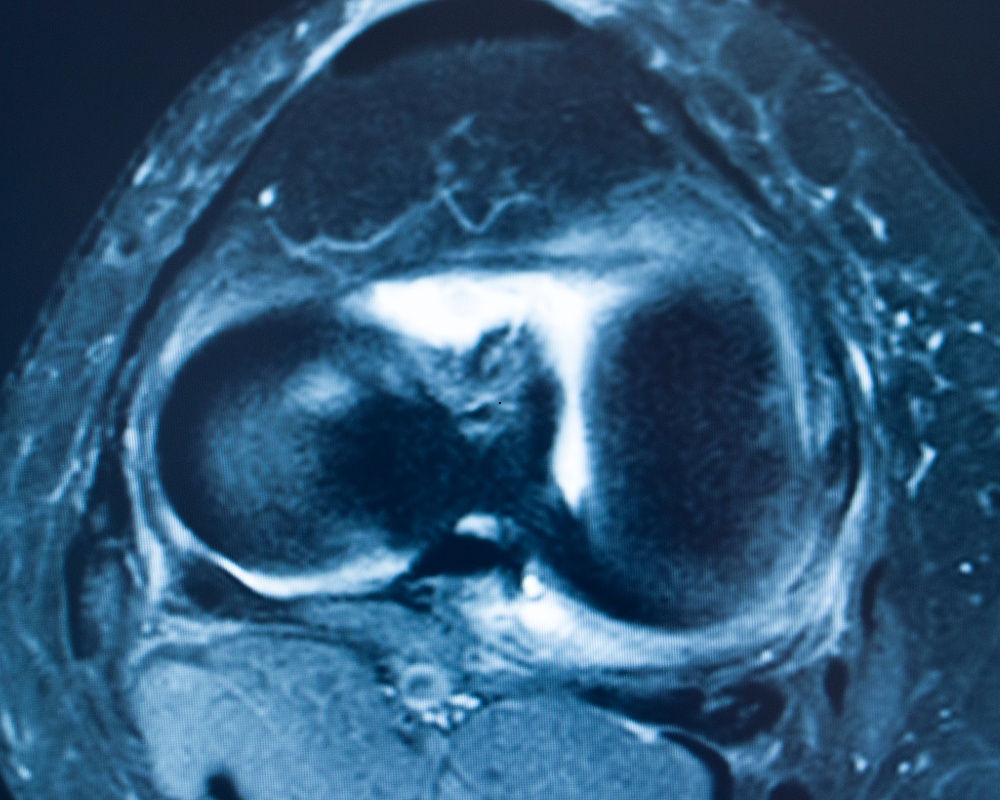

A follow-up magnetic resonance imaging (MRI) scan confirmed, I had an ACL tear. I chose not to have surgery.